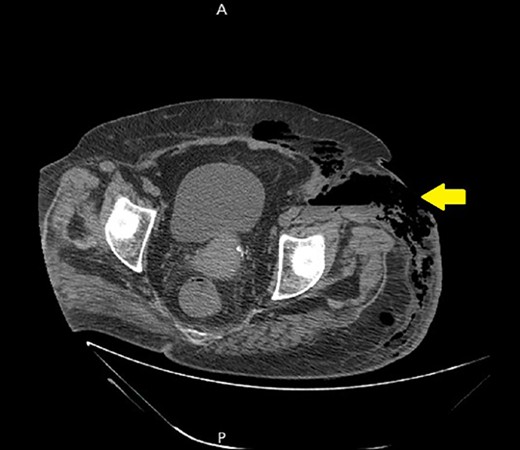

Ultrasound showed extensive subcutaneous soft tissue edema with hyperechoic areas seen in the proximal anterolateral part of the thigh. The initial diagnosis of the condition was a left iliopsoas abscess. Due to the severity of the patient’s symptoms, a non-contrast abdomen and pelvis computerized tomography (CT) scan was done (Fig. 3), which showed a large amount of subcutaneous emphysema within the left flank soft tissues that wrapped anteriorly along the left lower lateral abdominal wall with a small tract of air extending from the left retroperitoneum posterior to the left kidney and extending along the left iliopsoas muscle inferiorly. A skin defect with the underlying abscess collection and air–fluid level was noted (Fig. 4). Another CT scan section saw a soft tissue mass lesion at the distal descending colon (Fig. 5). The abscess drainage was done under CT guidance.

A non-contrast abdomen and pelvis CT scan, which shows a soft tissue mass lesion at the distal descending colon.